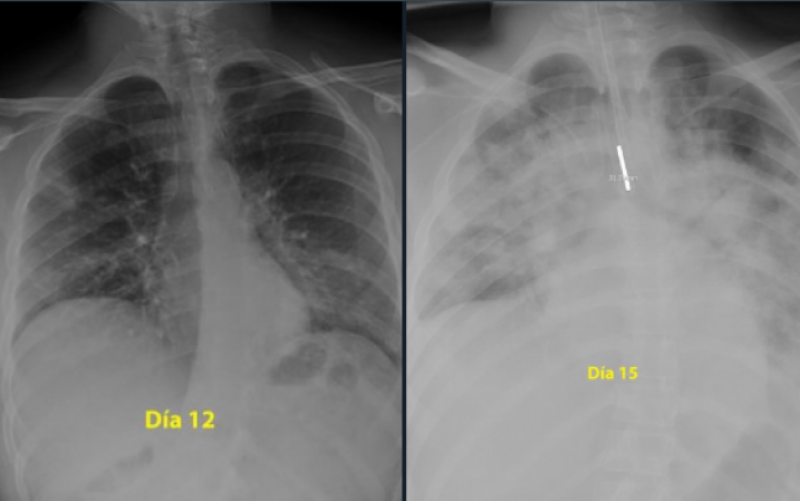

Potrivit adevarul.ro, un medic pneumolog din Spania a postat pe Twitter două radiografii care arată cum s-au degradat, în doar trei zile, plămânii unui tânăr de 28 de ani care a făcut o formă gravă de COVID-19. Momentan, noul coronavirus îi afectează, în general, mai puţin pe tineri, dar aceştia nu sunt totuşi, invincibili. Cercetătorii avertizeză că virusul suferă încă mutaţii.

„Pentru cei care cred că sunt nemuritori şi continuă să iasă în parc fără să acorde atenţie ordinului de a rămâne acasă, radiografiile unui băiat de 28 de ani intubat la Terapie Intensivă în spitalul meu, pentru coronavirus, arată gravitatea bolii”, a spus medicul, postând şi două fotografii cu plămânii tânărului, care, în doar trei zile de boală, au fost „măcinaţi” de pneumonie. „Plămânii sunt negri, albul este pneumonie”, a scris medicul pe Twitter.